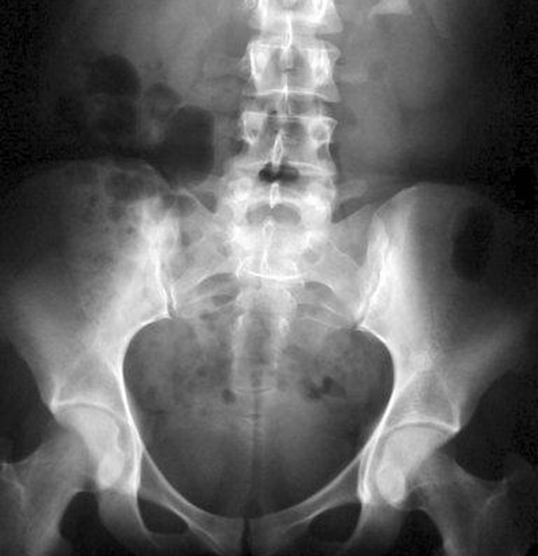

Запитання 26

НА ЯКІЙ РЕНТГЕНОГРАМІ Є КІСТКИ, ЩО НЕ НАЛЕЖАТЬ ДО СКЕЛЕТУ НИЖНЬОЇ КІНЦІВКИ?

варіанти відповідей

ДЕ ВИ БАЧИТЕ ЕЛЕМЕНТ КІСТКИ, ЗНАННЯ ЯКОГО НЕОБХІДНЕ В АКУШЕРСТВІ ДЛЯ ВИМІРЮВАННЯ РОЗМІРІВ ВЕЛИКОГО ТАЗУ? (ВЕРТЛЮГОВА ДИСТАНЦІЯ).

Запитання 34